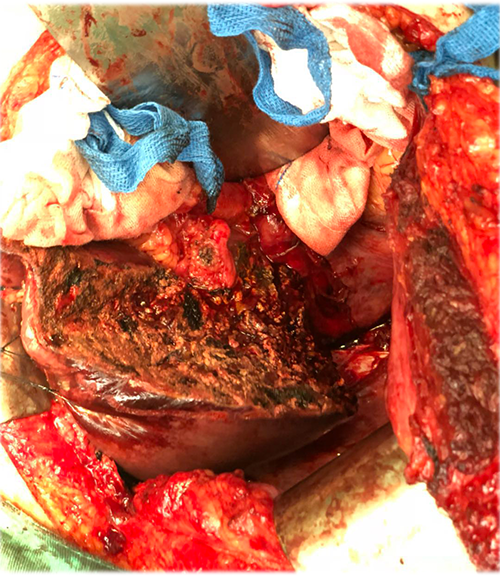

右肝癌----S567切除